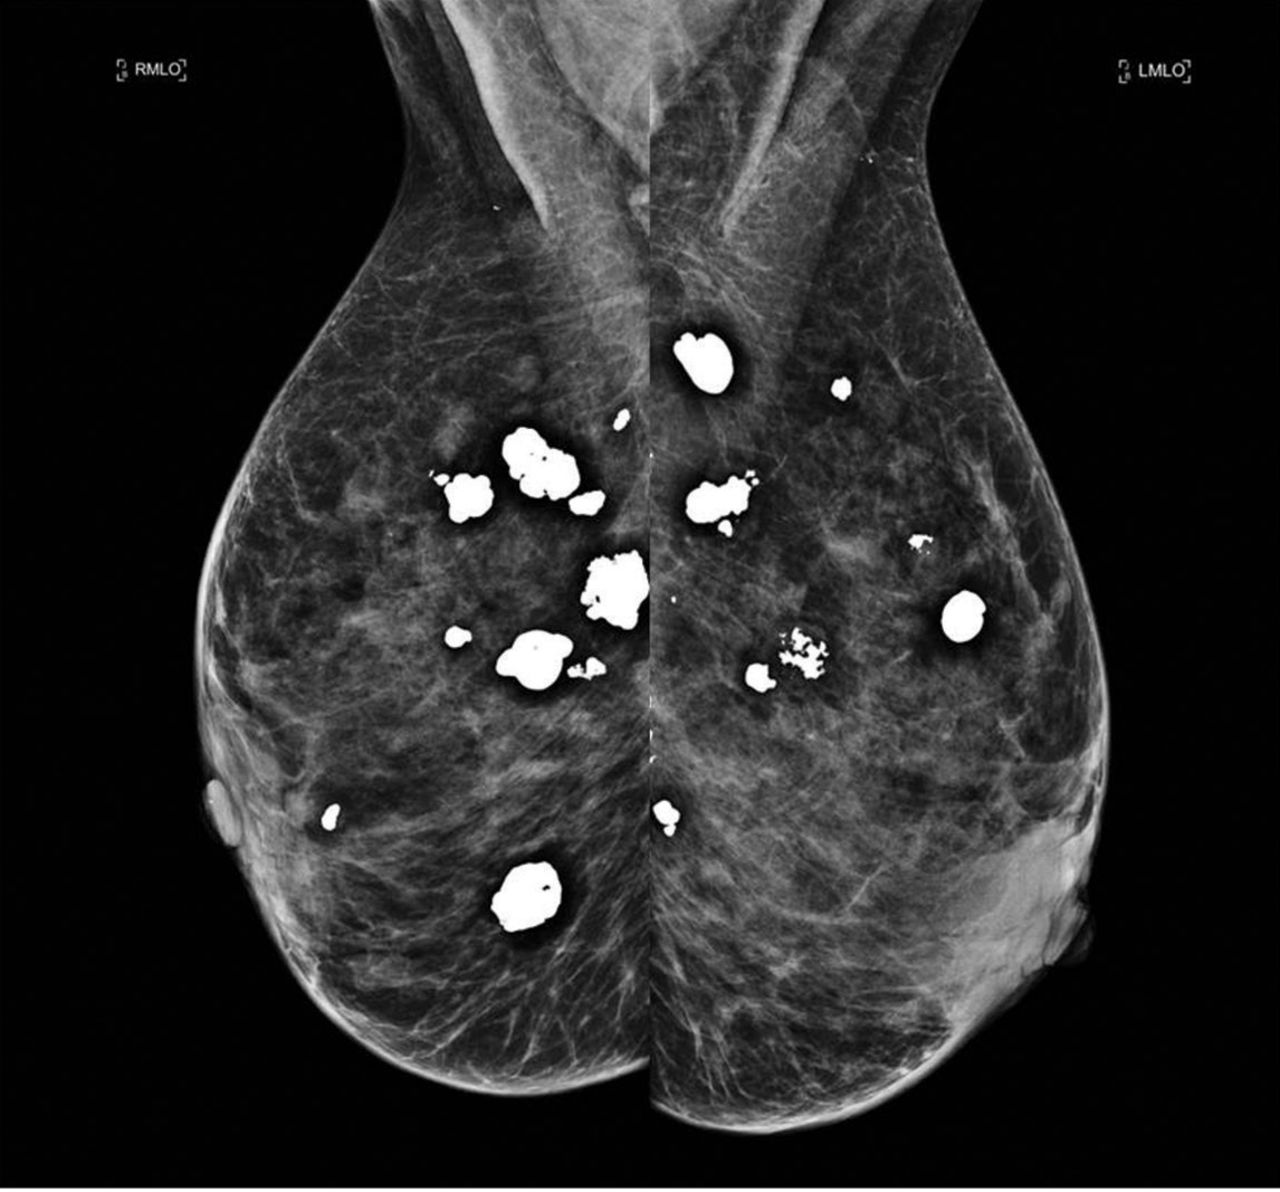

They appear as white spots or flecks on a mammogram but can't be felt during a breast exam. A new group has formed. For women treated for breast cancer in the past, calcifications may also be due.

There are numerous causes for calcium deposits in the breasts, including: But, japanese food natto has the ability to decalcify and maintain uniform level of calcium throughout the body and parts. Breast calcifications. california pacific medical center: